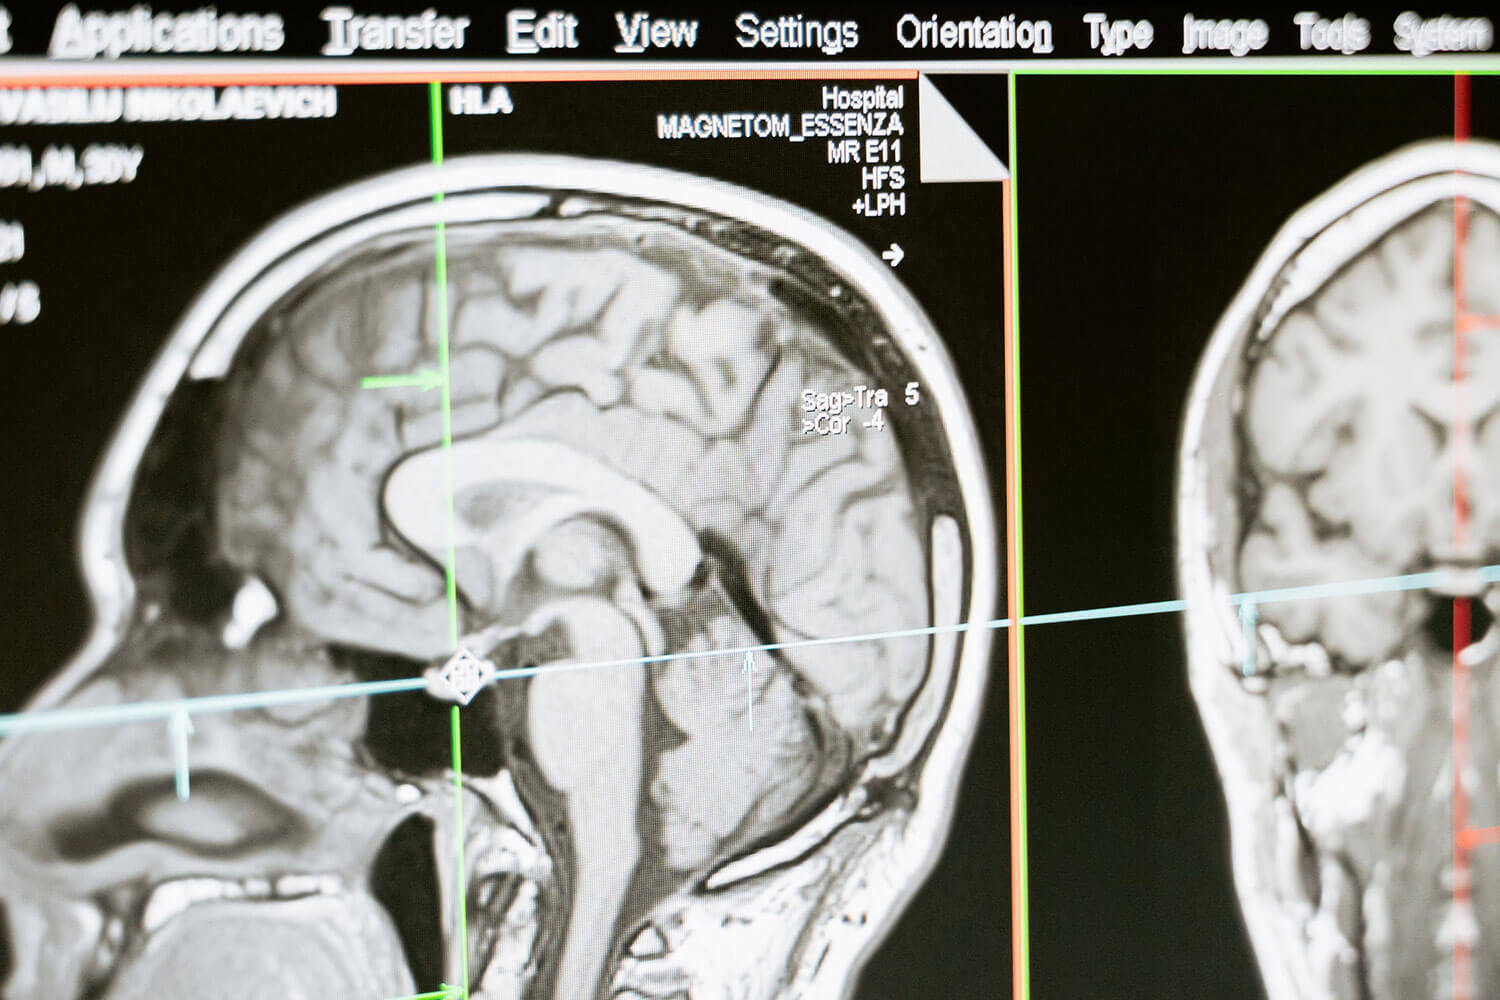

Exploring the Brain: How Head MRI Scans Can Uncover Hidden Neurological Conditions

Understanding Head MRI Scans Magnetic Resonance Imaging (MRI) has transformed our understanding of the human brain, offering valuable insights. At Reveal MRI, we utilize cutting-edge high-field open MRI scanners to capture detailed images, ensuring clarity and comfort throughout the scanning process. Unlike X-rays or CT scans, MRI uses powerful magnets and radio waves, eliminating the…